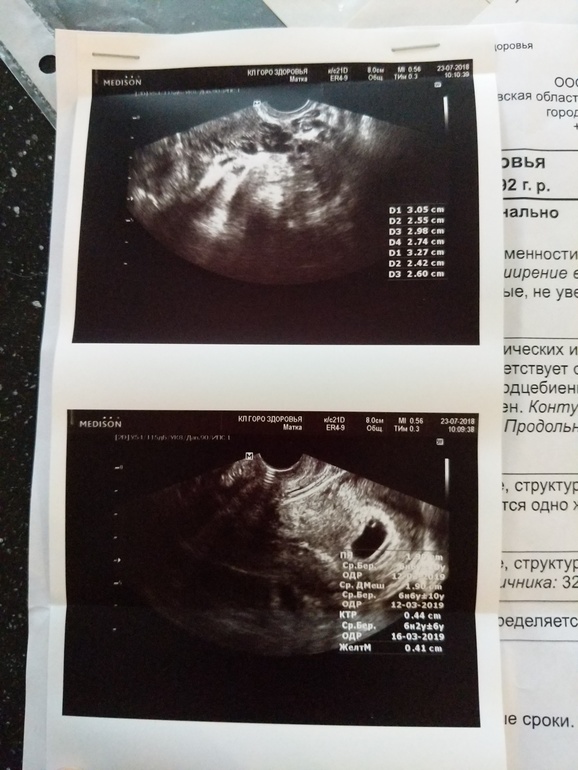

11дз.6 акушерских ПРИМЕРНО (бог его знает,когда была О и И)

УЗИ...ну что,прощай,Надежда.

Со слов узистки...

Плодное яйцо размерами на 4,5 недель,но есть желточный мешок. Что говорит о 5,5 недель.

Эмбриона не видно. ЖМ маленький,ПЯ маленькое.

До ряслись мои ноги и руки до УЗИ. Вроде,успокоилась,как задумалась,не маловат ли ктр?)